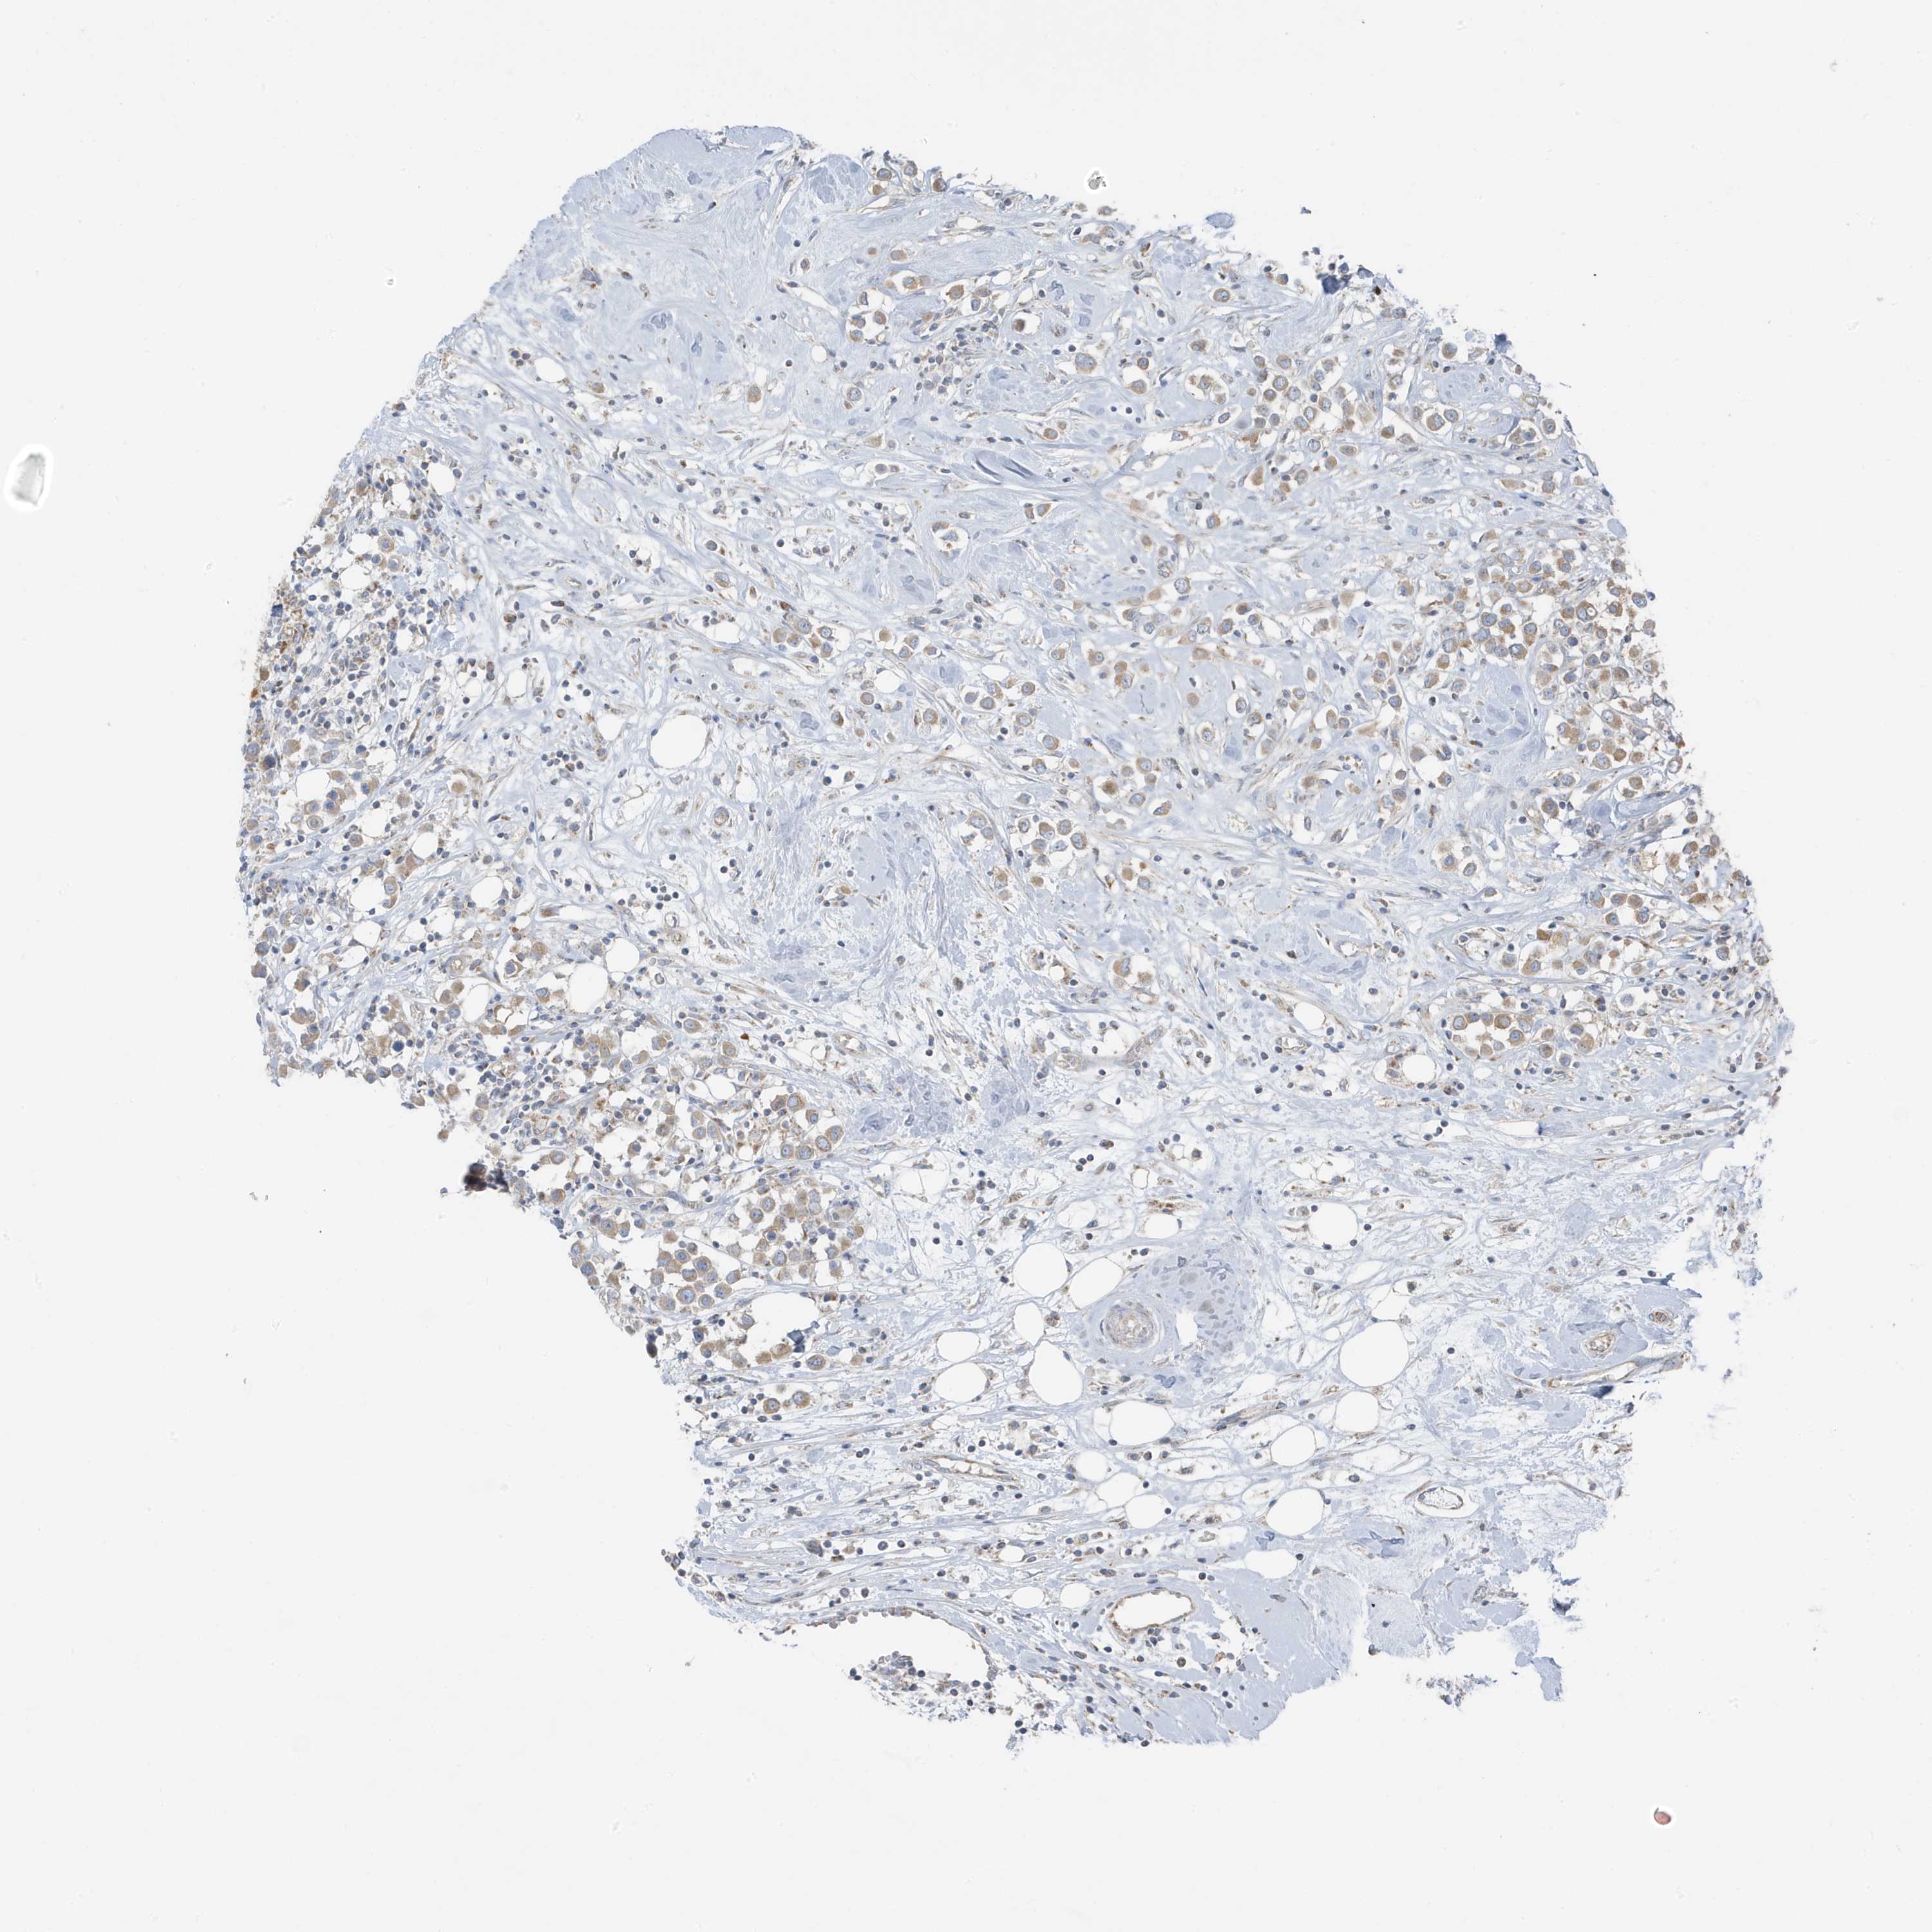

CANCER BREAST CANCER Show tissue menu

BRCA TCGA BRCA VALIDATION PROTEIN EXPRESSION